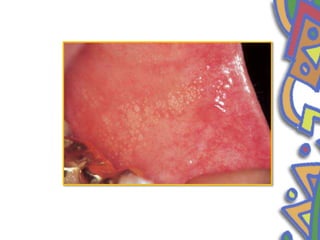

• Median rhomboidglossitis • Median rhomboid glossitis is clinically characterized by erythmatous lesion in the center of posterior part of dorsum of tongue • Developmental defect resulting from an incomplete desent of tuberculum impar and entrapment of a portion between fusing lateral halves of the tongue • 3:1 male predilection

• 37.

• rhomboid shaped,smooth erythmatous mucosa lacking in papilla or taste buds • atropic candidiasis

• 38.

• Clinical features •Present in the posterior midline of the dorsum of the tongue • Less than 2cm • Surface is smooth • lobulated

• 39.

• kissing lesion •Occasionally lesions are located somewhat anterior to usual location. None have been located posterior to circumvallate papilla